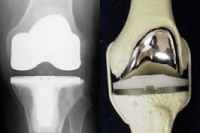

Реабілітація після ендопротезування колінного суглоба